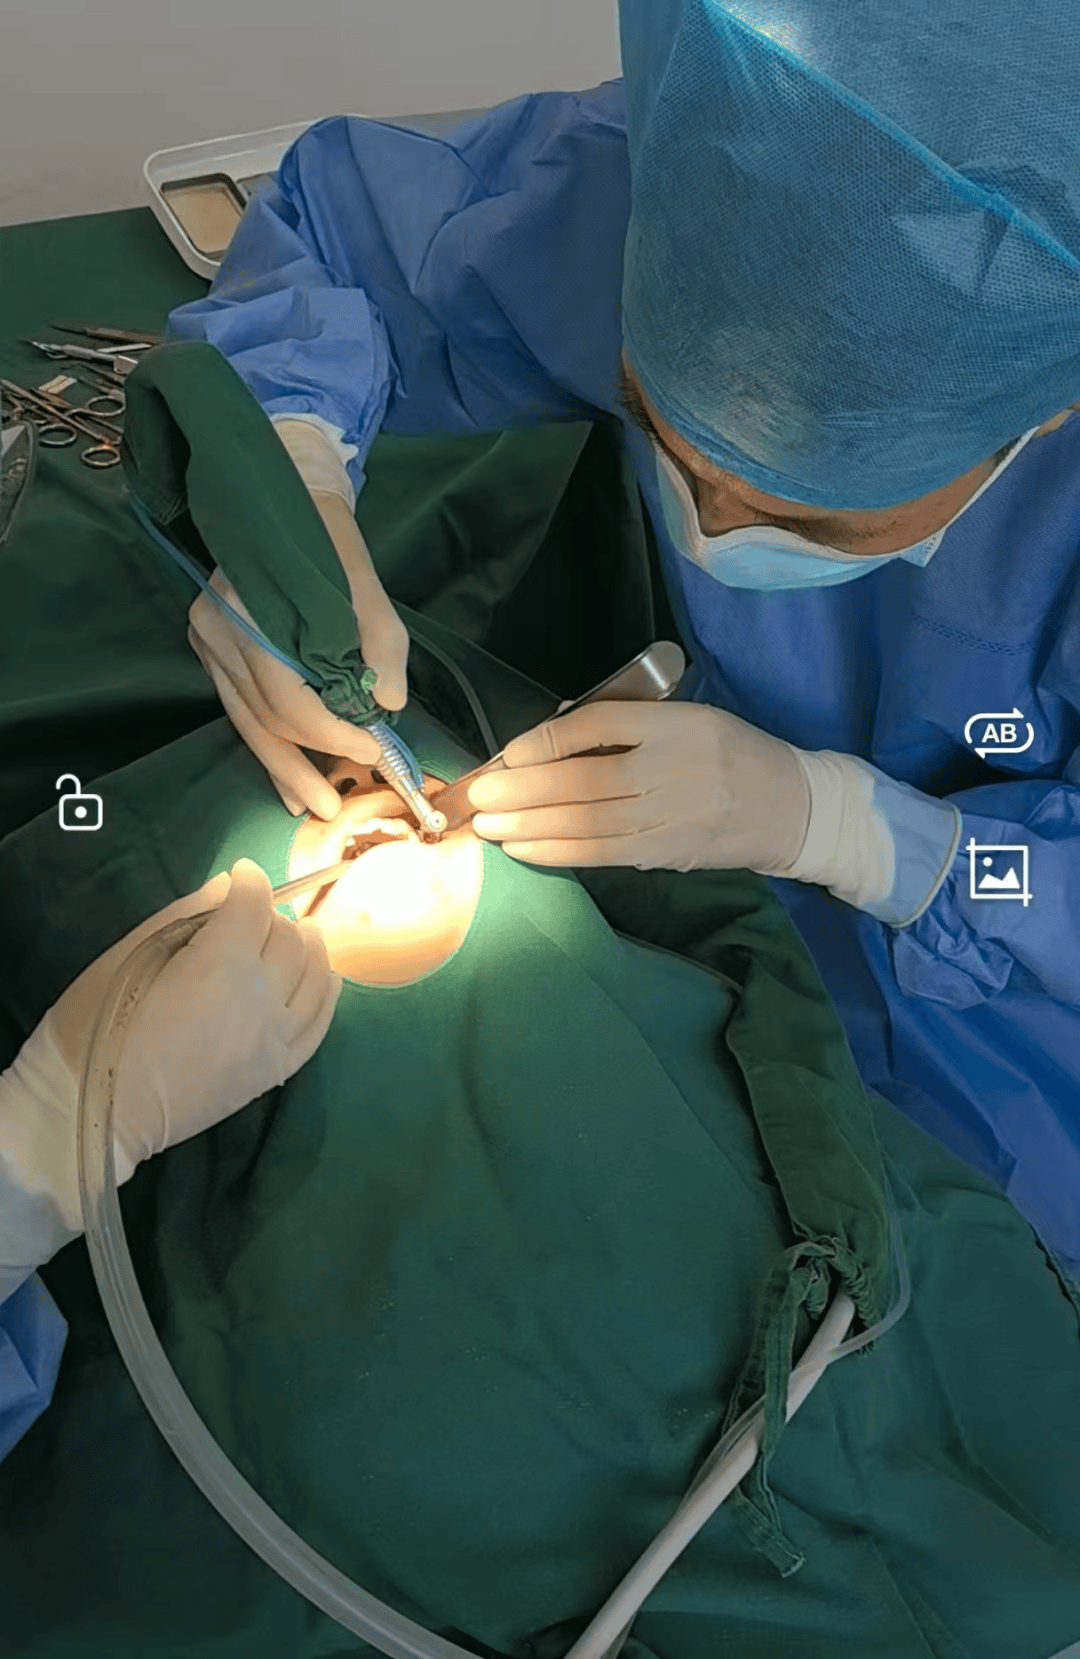

种植牙全过程|一期二期三期流程及时间详解种植体与骨组织的结合期通常为3-6个月,但亲水种植体可加快愈合,2-4周即可进行二期手术。二期:揭开牙龈的秘密 一期手术后的骨愈合期过后,进入二期手术。此时,医生会切开牙龈,移除覆盖基台,换上愈合基台以促进牙龈愈合,缝合伤口。整个过程约半小时,尽管有些人可能觉得安装基台过程略感疼痛,但总体...

正畸牙周植骨——PAOO手术在开始正畸前,常规的洗牙、牙龈刮治和补牙拔牙为牙齿健康打下了基础。上牙套初期,牙齿对力度调整有所反应,虽然短暂不适,但很快就能适应。随着进程,植入支抗钉并开始牵引皮筋,助力牙齿移动。一年后,医生建议我进行牙周植骨,原因是为了避免正畸过程中对牙齿造成不可逆的损伤。面对PAOO手术,我虽有过...

种牙齿的过程和时间种牙齿的过程总共需要36个月的时间,并且往往需要复诊35次。具体过程如下:检查:首先进行详细的检查,包括X光片、口腔CT和验血等,以评估患者的口腔状况和种植牙的可行性。一期手术:根据检查结果,预约手术时间,在手术当天将种植体植入牙槽骨内。根据患者情况,可能还需要进行植骨手术。如果初期稳定性较好...